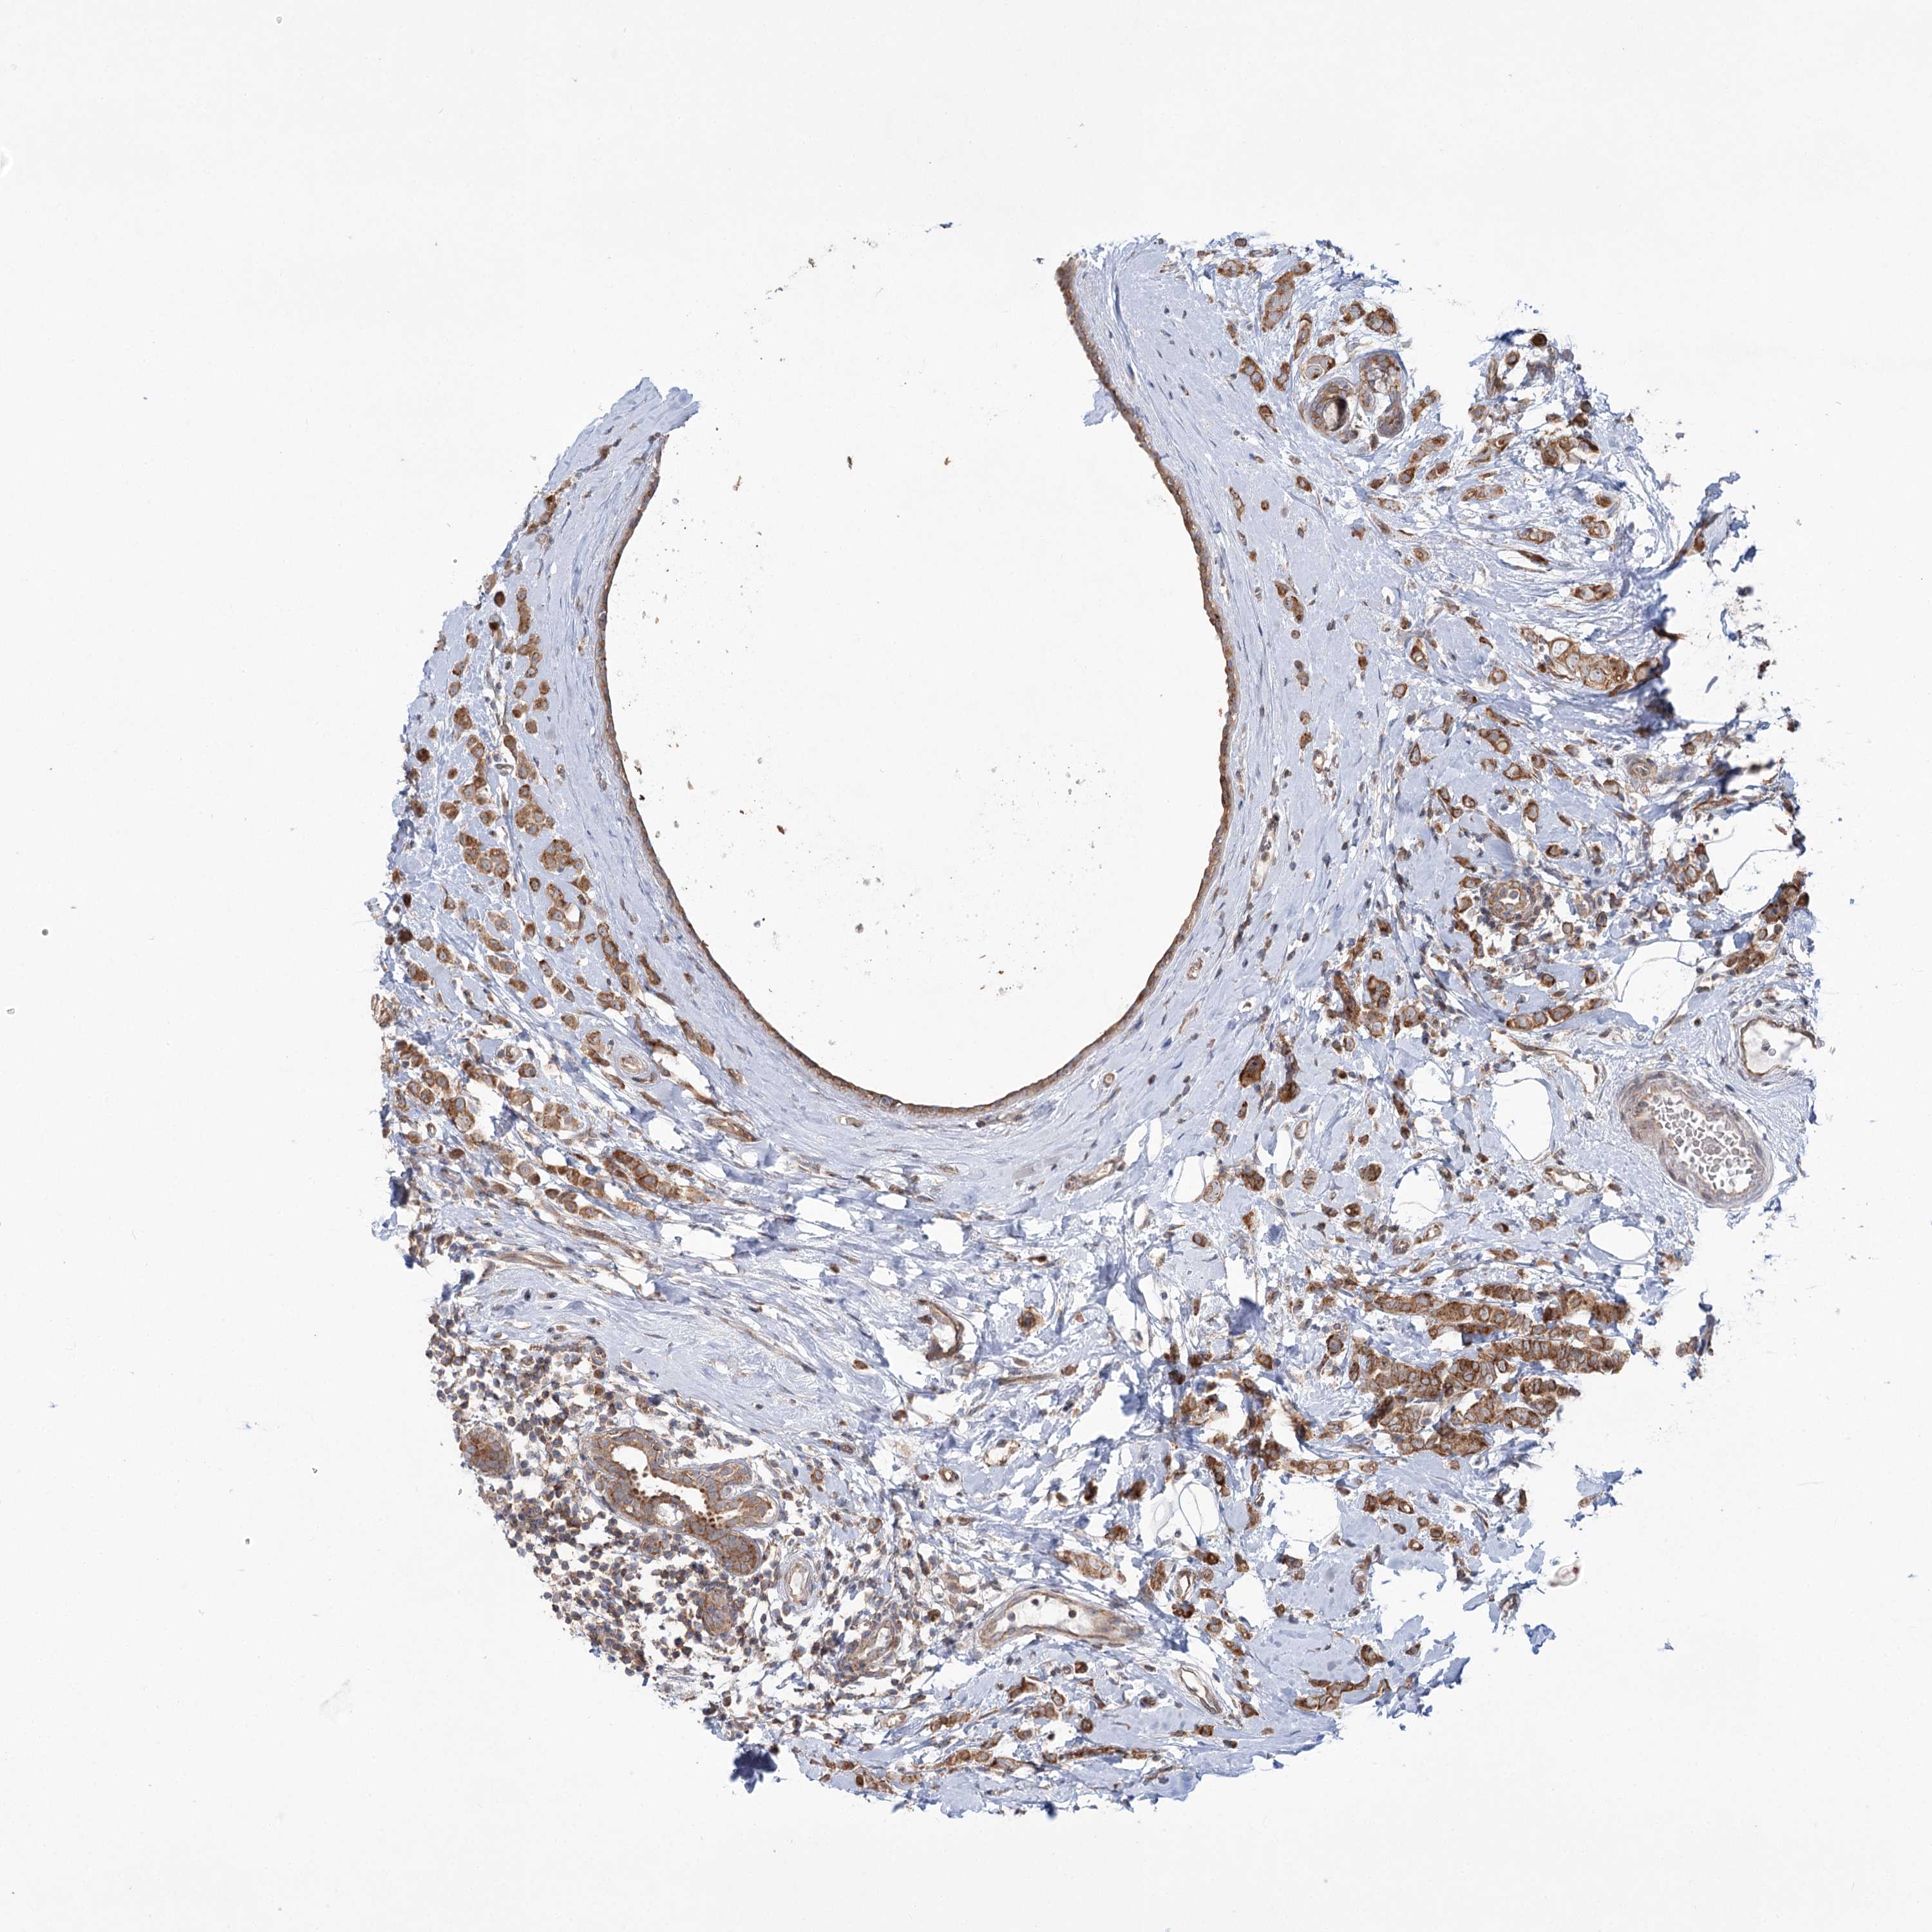

CANCER BREAST CANCER Show tissue menu

BRCA TCGA BRCA VALIDATION PROTEIN EXPRESSION

ANTIBODIES

AND

VALIDATION